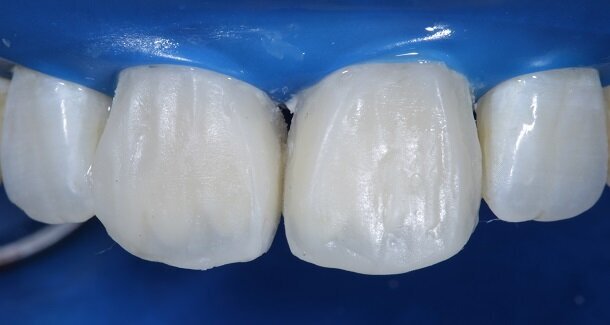

The figures show the clinical work flow involved. In the 1st appointment Oral prophylaxis, oral hygiene instructions were followed by an impression that was sent to the lab for a wax up [Fig 3 and 4]. In the subsequent appointments, Endodontic treatment was followed by Intra and extra coronal office bleaching using the Pola office bleaching kit. After two weeks, the shade stabilised post bleaching. Shade selection, rubber dam isolation and preparation was done on both the teeth to receive Direct composite veneers so as to close the midline diastema as well as correct the fractured teeth and the slight mal-alignment. Controlled Body Thickness (CBT) technique of layering was used with 3M Z350XT shades - Dentin shades A3, A2 and Enamel shades A2, clear translucent [Figures 5 to 11]. This was followed by the Finishing and polishing protocol as described in the figures.

Fig 12- Gross finishing for the outline of the tooth was achieved using Red ring (composite finishing) tapered rounded bur. Almost 80% of the finishing can be done using this bur. It also helps in creating surface macro and micro anatomical variations. For better control, this bur can be used on a contra-angled hand-piece along with a convertor.

Fig 13 and 14 -Transitional Line angles were marked using a pencil and made prominent using medium grit 3M Soflex Discs proximally. The apparent faces of both the teeth were thus, created.

Fig 15 and 16 - For the surface texture; vertical surface macro-anatomy showing developmental grooves (mesial and distal) were marked using a pencil and created using the red ring finishing bur.

Fig 17- Horizontal surface micro-anatomy, that is, the Perikymata or imbrication lines were marked cervically and incisally, using a pencil and created using the red ring finishing bur.

Fig 18 - Pre-polishing was done using a 3M soflex white spiral under pressure on a contra-angled handpiece.

Fig 19 and 20 - Polishing was done by using 3M soflex beige and purple spirals in sequence.

Fig 21 - Final polishing for high gloss was done using a dry Buff (unidirectional, high speed and feather touch).